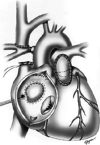

Surgical strategies in patients with functionally or anatomically borderline right ventricles include a high-risk biventricular repair, a Fontan procedure, or a one and half ventricle repair (also referred to as the partial biventricular repair). One and half ventricle repair (1.5VR) circumvents the high early mortality of a biventricular repair and also the late morbidity of the Fontan. The two most common indications for a 1.5VR are a small pulmonary ventricle and a dilated poorly functioning pulmonary ventricle. Extension of 1.5VR to patients undergoing anatomical repair for congenitally corrected transposition of great arteries, straddling tricuspid valves, and severe Ebstein's anomaly has facilitated biventricular repair with decreased mortality. We reviewed the relevant literature on this subject in detail and describe its rationale, indications and its early and late results.